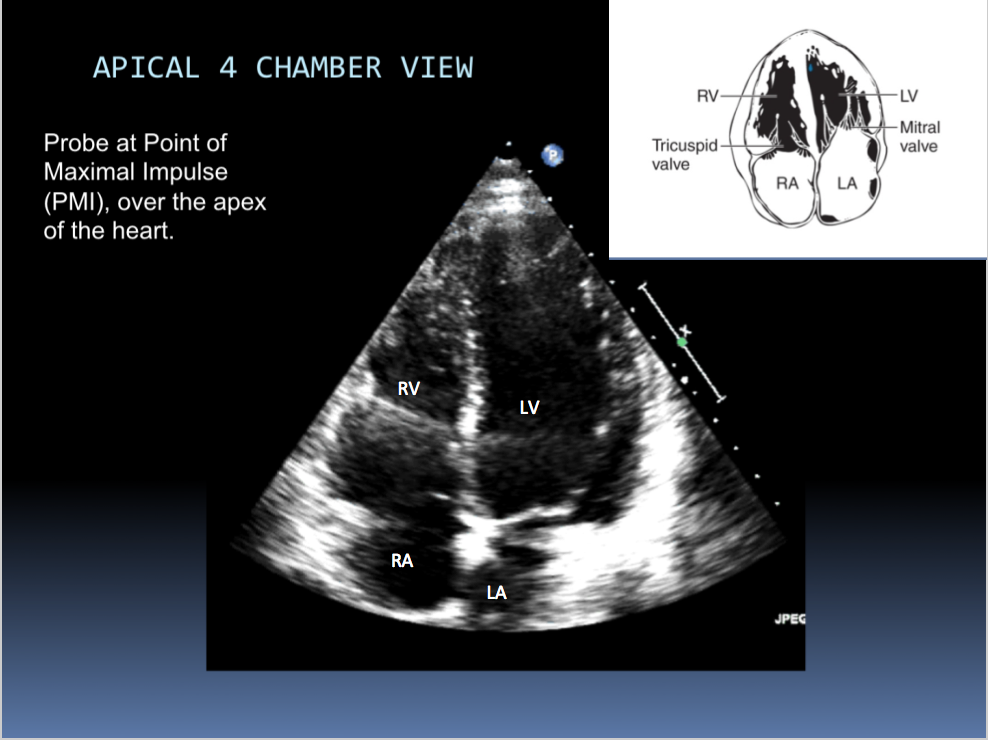

Identify the chambers shown in this image: